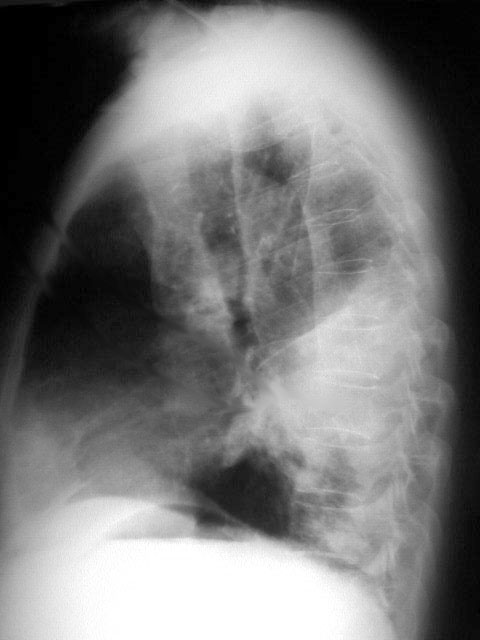

Este signo tiene el mismo significado que el signo del broncograma aéreo. La orientación del bronquio 6 (segmento apical del lóbulo inferior) hace que en vez de ver el broncograma como en otros lóbulos -dibujándose el trayecto bronquial- lo veamos de frente: sólo se ve una imagen redondeada de menor densidad que la consolidación (flecha).

La radiografía lateral confirma la localización en el segmento 6.